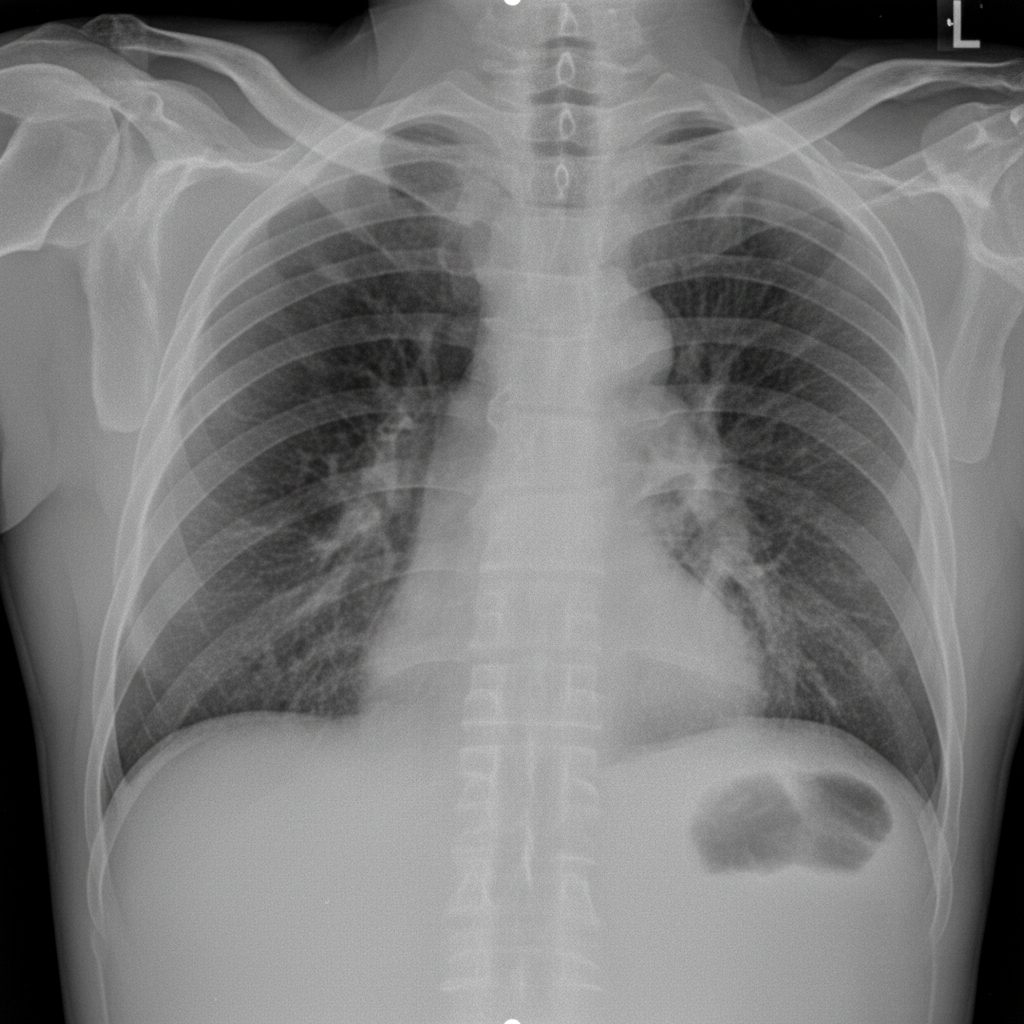

The X-ray demonstrates which of the following conditions?

Explanation: ***Perforation peritonitis*** - **Free air under the diaphragm** (pneumoperitoneum) on erect chest X-ray is the pathognomonic sign of gastrointestinal perforation. - Results from rupture of a hollow viscus allowing air to escape into the peritoneal cavity, causing **acute peritonitis**. *Intestinal obstruction* - Characterized by **air-fluid levels** in dilated bowel loops on X-ray, not free air under diaphragm. - Presents with **colicky abdominal pain** and vomiting, but lacks signs of perforation like pneumoperitoneum. *Paralytic ileus* - Shows **diffuse bowel dilation** with gas throughout small and large bowel without air-fluid levels. - Absence of **peristalsis** leads to gaseous distension, but no free intraperitoneal air is present. *Chilaiditi's syndrome* - **Colonic interposition** between liver and diaphragm can mimic free air but shows **bowel wall markings**. - Usually **asymptomatic** and represents a normal anatomical variant, not an acute pathological condition.